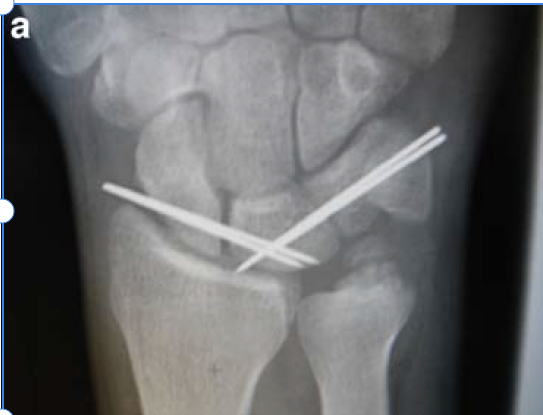

Procedimiento endoscópico para el síndrome del túnel carpiano: recuperación rápida con menos dolor

Descubre el procedimiento endoscópico para el síndrome del túnel carpiano, que ofrece una recuperación rápida y menos dolorosa, permitiendo a los pacientes retomar sus actividades casi de inmediato.